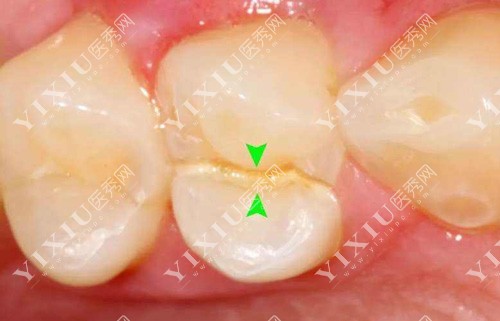

3M350补牙(适合后牙):399元起

3MP60补牙(适合后磨牙):529元起